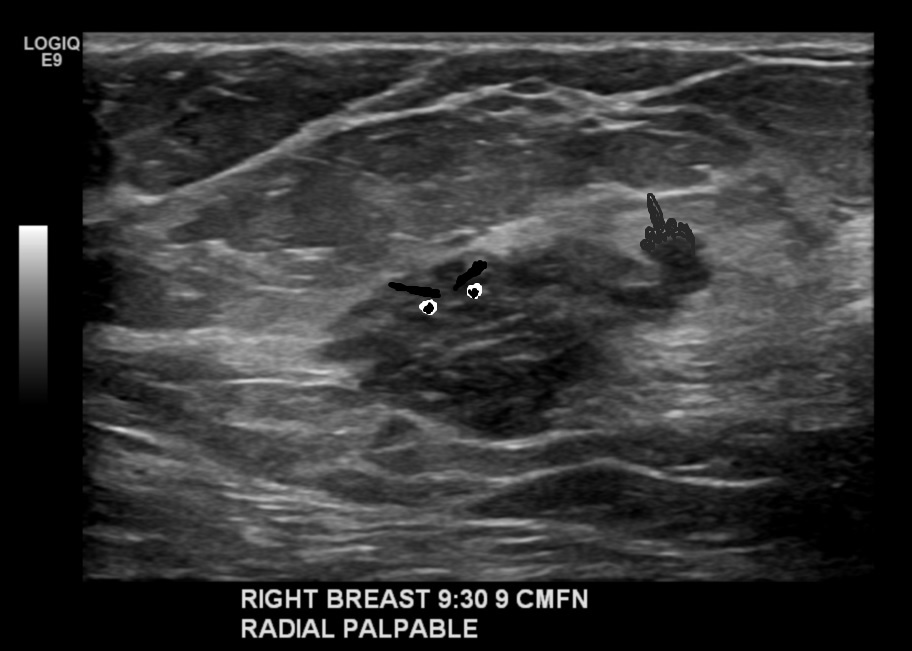

Beyond waiting, the thing that’s irritating me is the possibility of getting chemo/hormone therapy before surgery. It’s not uncommon, it seems to be very effective, and yet I feel like I don’t want to do it that way. For one thing, Turdy is fucking annoying me. He’s shape-shifting inside my tit, and as he is both HER2 positive AND according to his Ki-67 levels 50% of his shitty little self is in mitosis, he’s probably GROWING. You can almost see him from the outside now, in profile. He’s lumpier than before. He might be flipping me off. I want him OUT. I am starting to feel empathy for the crew of the Nostromo.